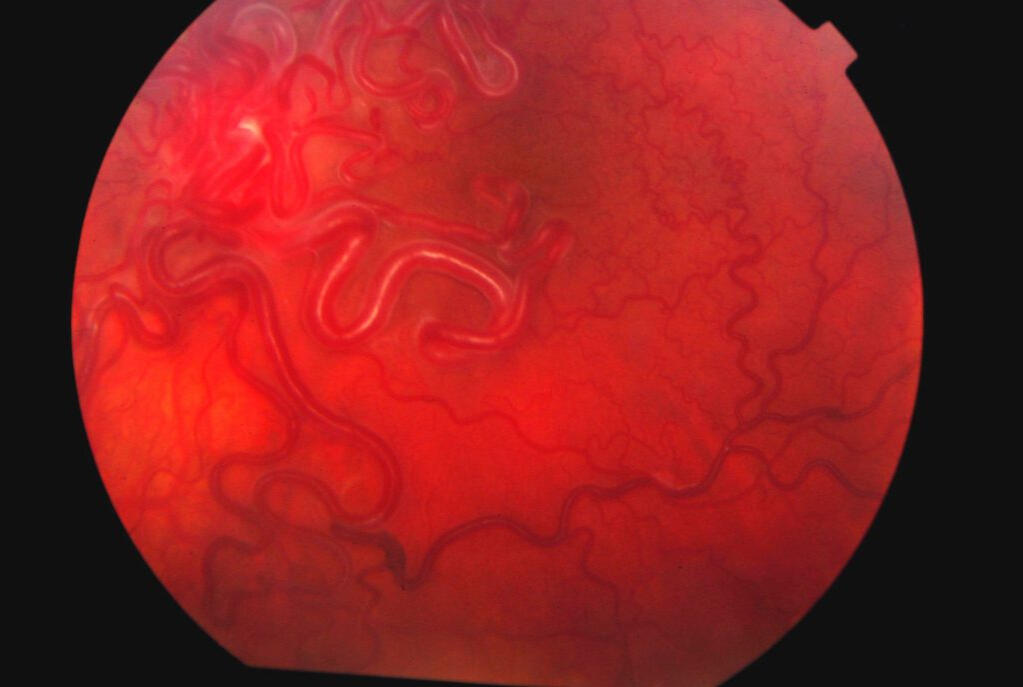

75. Retinal Migraines

122. The Tumour

Unfortunately, the MRI scans of my tumour have been lost. But this gives you a pretty good idea. Image courtest of Mayfield Clinic